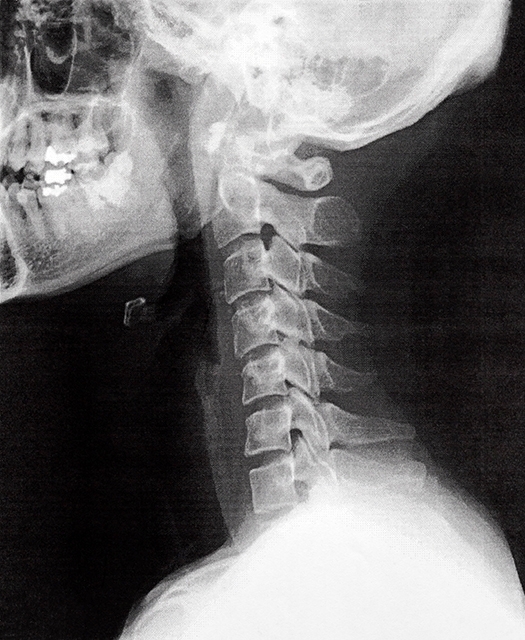

スマホ首=ストレートネックと呼ばれ

本来カーブのある頚椎ですが長期間下を向くことにより

カーブが失われた状態を言います。